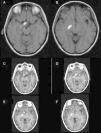

Case reportA 30-year-old female with a preoperative radiological diagnosis of dermoid cyst was operated. No lesion was found in the chiasmal or carotid cisterns within the operative field. The right posterolateral corner of the chiasma and the beginning of the right optic tract appeared swollen. The area was incised and a haemorrhagic fluid poured through the opening. Several samples were taken and the pathological diagnosis was of pilocytic glioma.

ConclusionsWe present a unique case of chiasmal bleeding into the optic pathway secondary to an optic glioma which radiologically mimicked an intracisternal cyst. In similar cases, rapid clinical evolution of the symptoms may be vital for the differential diagnosis. Surgery is warranted to prevent permanent damage to the visual pathway.